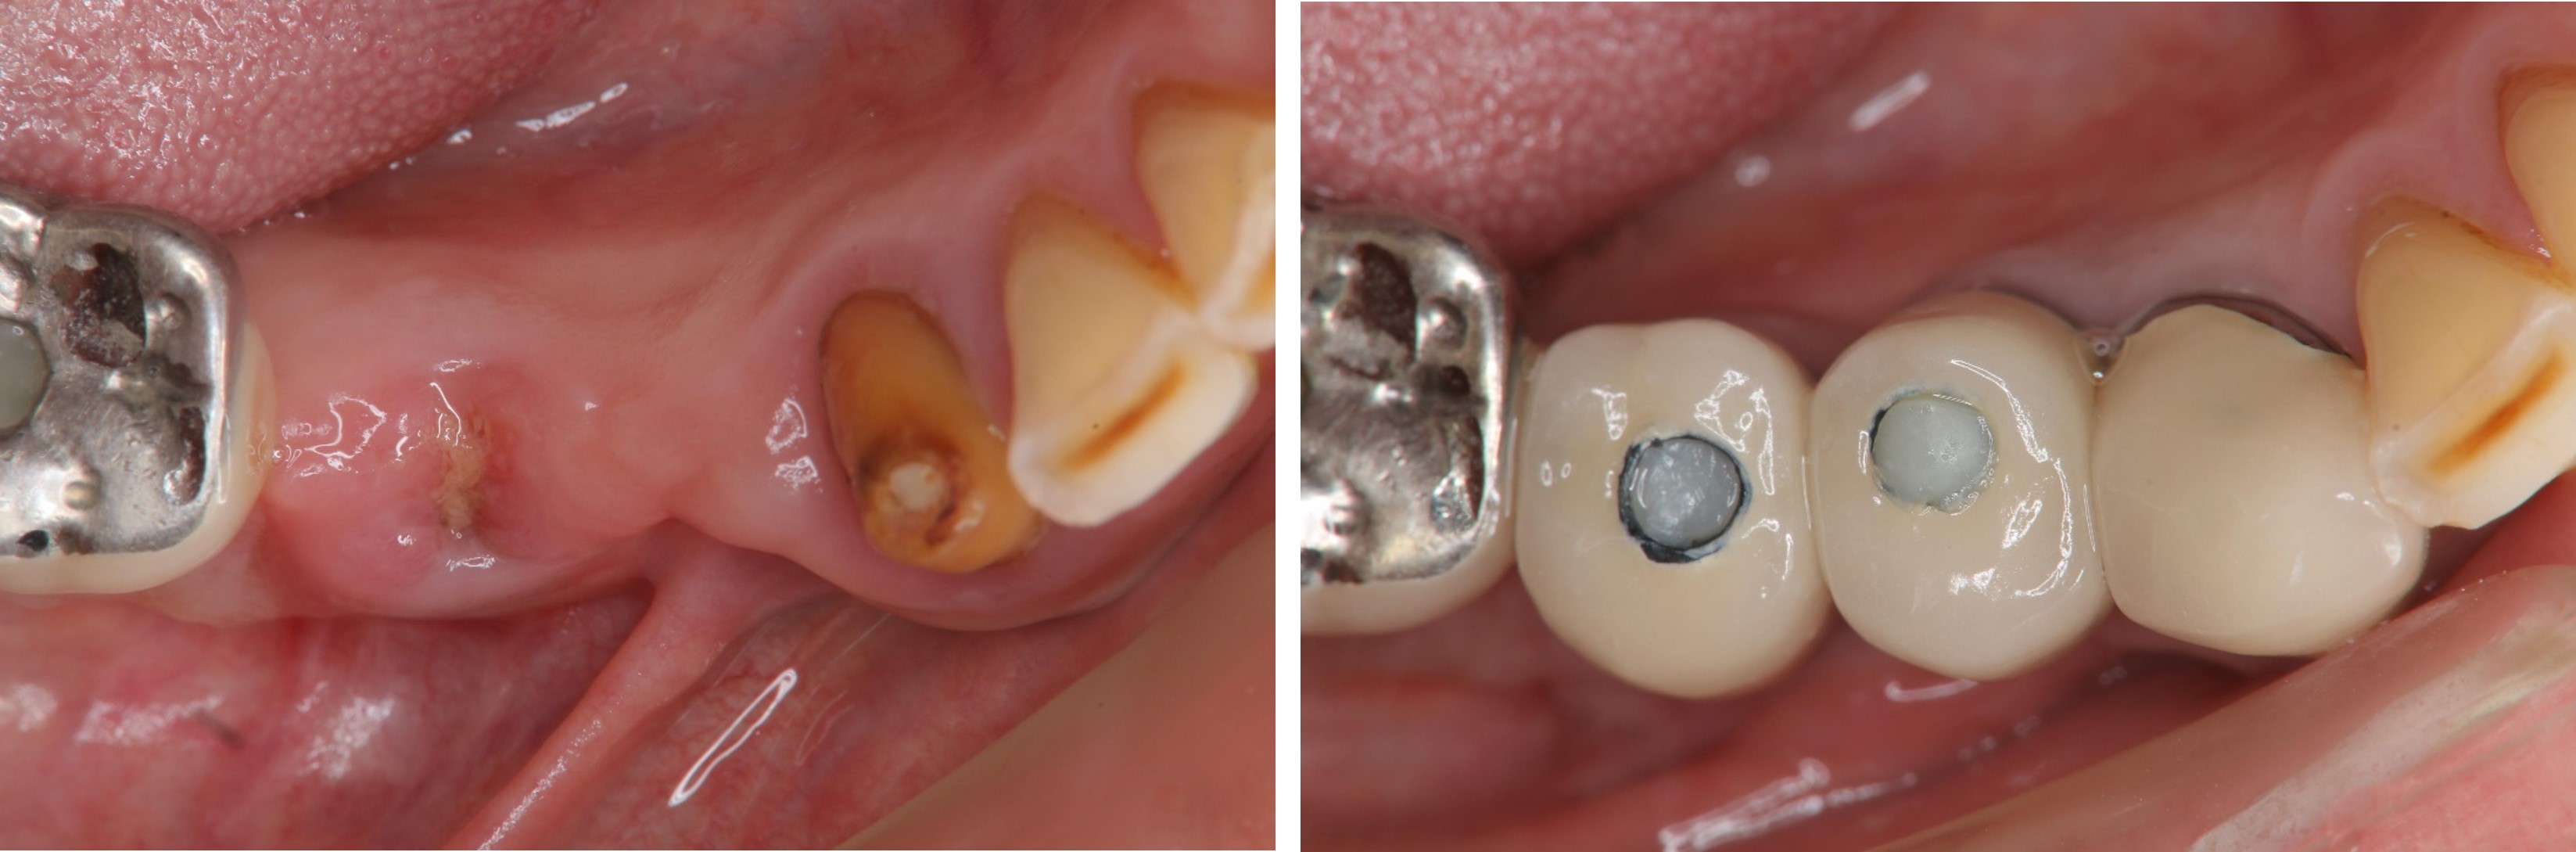

術前、術後比較

治療後口內照